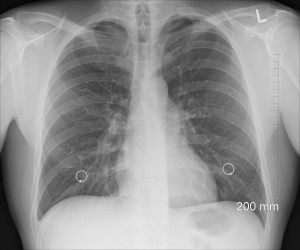

Lungenröntgen: Sterblichkeit bei Krebs untersucht (Foto: pixabay.com, oracast) |